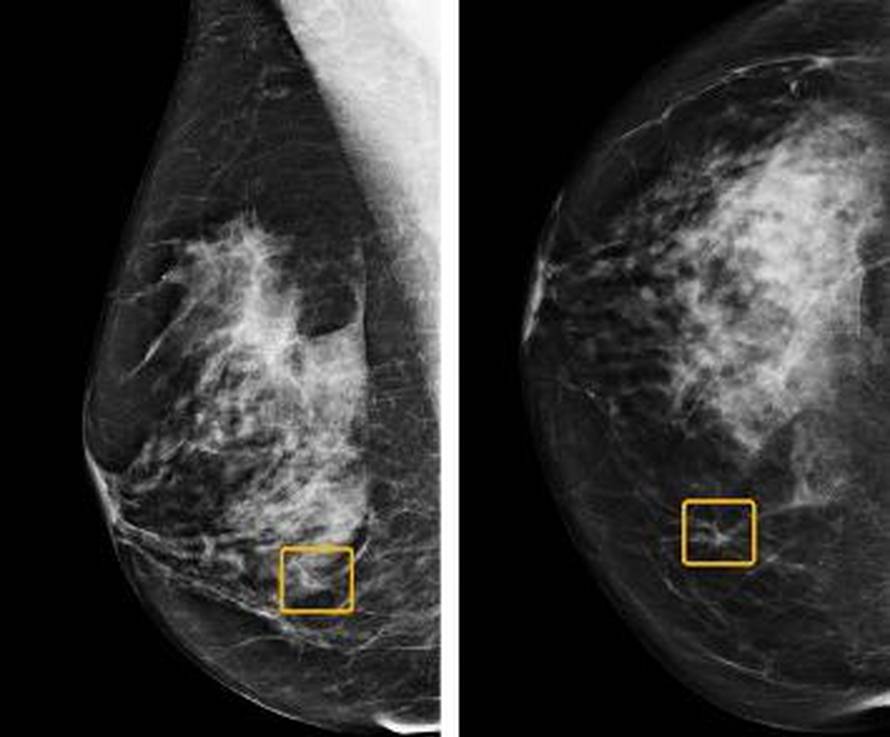

Sustav umjetne inteligencije baziran na algoritmu pokazao se učinkovitijim od radiologa u prepoznavanju raka dojke s mamografa, a bolje je uočavao i lažno pozitivne ili negativne dijagnoze